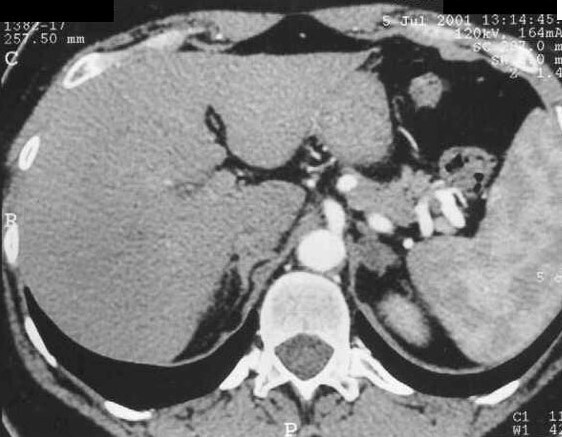

On recherche donc un adénome de Conn. L’examen d’imagerie de référence est le scanner abdominal sans et avec injection avec coupes fines sur les surrénales (généralement < 2 cm, hétérogène, hypodense < 10 UH, faible rehaussement et lavage rapide).

Voici le résultat du scanner :

Question 13 - Quel est votre diagnostic ?

Adénome de Conn devant l’association :

– d’un hyperaldostéronisme primaire ;

– d’une image surrénalienne typique.

Lorsque l’imagerie est plus litigieuse, il est possible de réaliser un cathétérisme simultané des veines surrénaliennes. La sécrétion est considérée comme latéralisée en présence d’un rapport aldostérone sur cortisol supérieur à 5 d’un côté ou l’autre (le dosage du cortisol permet de standardiser la sécrétion d’aldostérone).